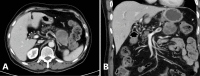

The rhabdoid subtype of undifferentiated pancreatic carcinoma is rarely reported. The clinical course of this disease is therefore poorly understood, although it is apparently an aggressive malignancy. We herein discuss the case of a 69-year-old man presenting with a rapidly enlarging mass of the pancreatic body and tail who was diagnosed with locally advanced SMARCB1-deficient undifferentiated pancreatic carcinoma with rhabdoid features, treated with radical resection and adjuvant chemotherapy, and has achieved 18-month disease-free survival ongoing at the time of article publication. We identify and contrast our case with 15 similar tumors reported in the English literature, briefly discuss the biology of this tumor, its relationship to malignant rhabdoid tumors of childhood, the role of SMARCB1 and its parent complex switch/sucrose-non-fermentable chromatin remodeling complex (SWI/SNF) in modulating the behavior of pancreatic malignancy, and the potential therapeutic avenues available for SWI/SNF-mutated malignancies.